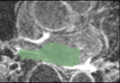

Auto-segmentation mask and cropped LGE image example.

| current | 08:47, 29 November 2011 | 695 × 478 (213 KB) | Ggardner (talk | contribs) | Auto-segmentation mask and cropped LGE image example. |